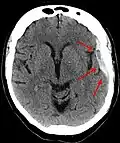

Sur le scanner crânien, fait sans injection de produit de contraste, l'hématome sous-dural se présente habituellement sous une forme de croissant, dont la concavité suit la courbe du cerveau, stoppé seulement par les réflexions durales telles que la faux du cerveau et le tentorium. Cependant ils peuvent avoir une forme convexe, spécialement tout au début du saignement, ce qui peut les faire confondre avec les hémorragies épidurales (hématome extradural). Le sang peut être vu comme une densité stratifiée tout au long du tentorium. Dans les cas chroniques, on peut voir l'effacement des sillons ou le déplacement médian de la jonction substance blanche/substance grise, mais le sang peut avoir une densité très proche de celle du tissu cérébral (isodense), ce qui peut masquer l'hématome.

Les hématomes sous-duraux sont plus fréquents dans les parties supérieure et latérales du frontal et au niveau des lobes pariétaux[5],[12] ainsi que dans la fosse postérieure proche de la faux du cerveau et de la tente du cervelet[5].